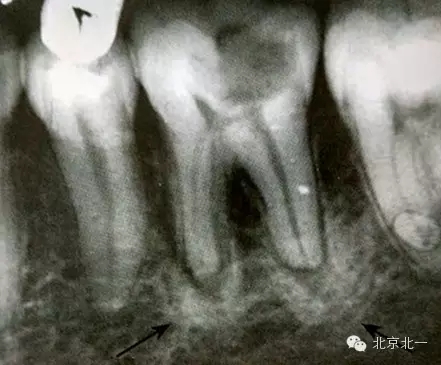

【CBCT表現(xiàn)】:發(fā)生致命性骨炎的環(huán)亞暢游牙體病變,其CBCT表現(xiàn)為圍繞根尖的骨質(zhì)密度增高區(qū),骨小梁增多增粗,骨髓腔變窄甚至消失,與正常骨組織分界不明顯。根尖部牙周膜間隙可增寬,根尖無增粗膨大。

根尖片顯示D6深齲,根尖低密度區(qū)周圍骨小梁增粗、增多,骨質(zhì)密度增高,骨髓腔變?。ê谏^)。

【CBCT表現(xiàn)】:

在CBCT上,根尖型骨島無低密度帶狀影包繞,與周圍骨質(zhì)分界清晰,具有特征性的毛刷樣邊緣,且其發(fā)生區(qū)域的牙根牙周膜影像連續(xù)、完整、不導(dǎo)致頜骨的膨隆。

右下頜C4根尖區(qū)課件一類圓形高密度影,與周圍骨質(zhì)分界清晰,C4牙周膜影像連續(xù)、完整,下頜骨未見膨隆。